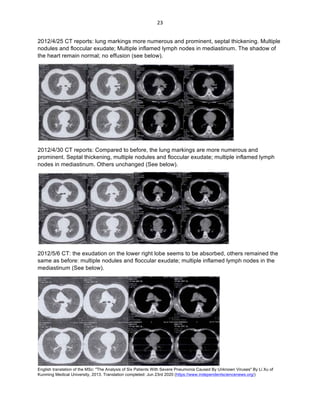

2012/5/16 – 2012/6/10 Chest film comparison (see below)

2012/6/6 – 2012/6/10 Analysis of the blood gas (see below)

Blood sugar

Lactic acid